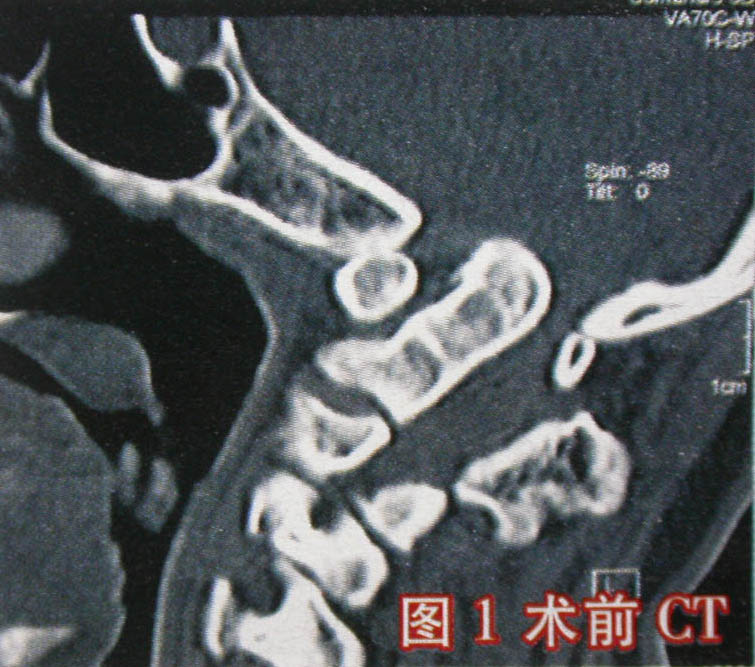

近日,北京大学第三医院骨科颅椎外科专业组采用创新术式,成功地为1例枕大孔区(颅椎区)复杂畸形,并继发严重寰枢关节脱位的19岁患者实施了手术治疗。患者入院时寰枢关节已呈完全脱位状态,枢椎齿突上移入枕大孔(图1),脊髓受压出现严重功能受损(图2),患者已有全身瘫痪、呼吸功能不全表现。该专业组王超主任医师等采用经口咽入路寰枢关节松解复位术和后路枕颈固定植骨融合术,使患者寰枢关节得以复位固定,其受压脊髓得到彻底减压。术后患者已恢复行走功能,日前已出院。